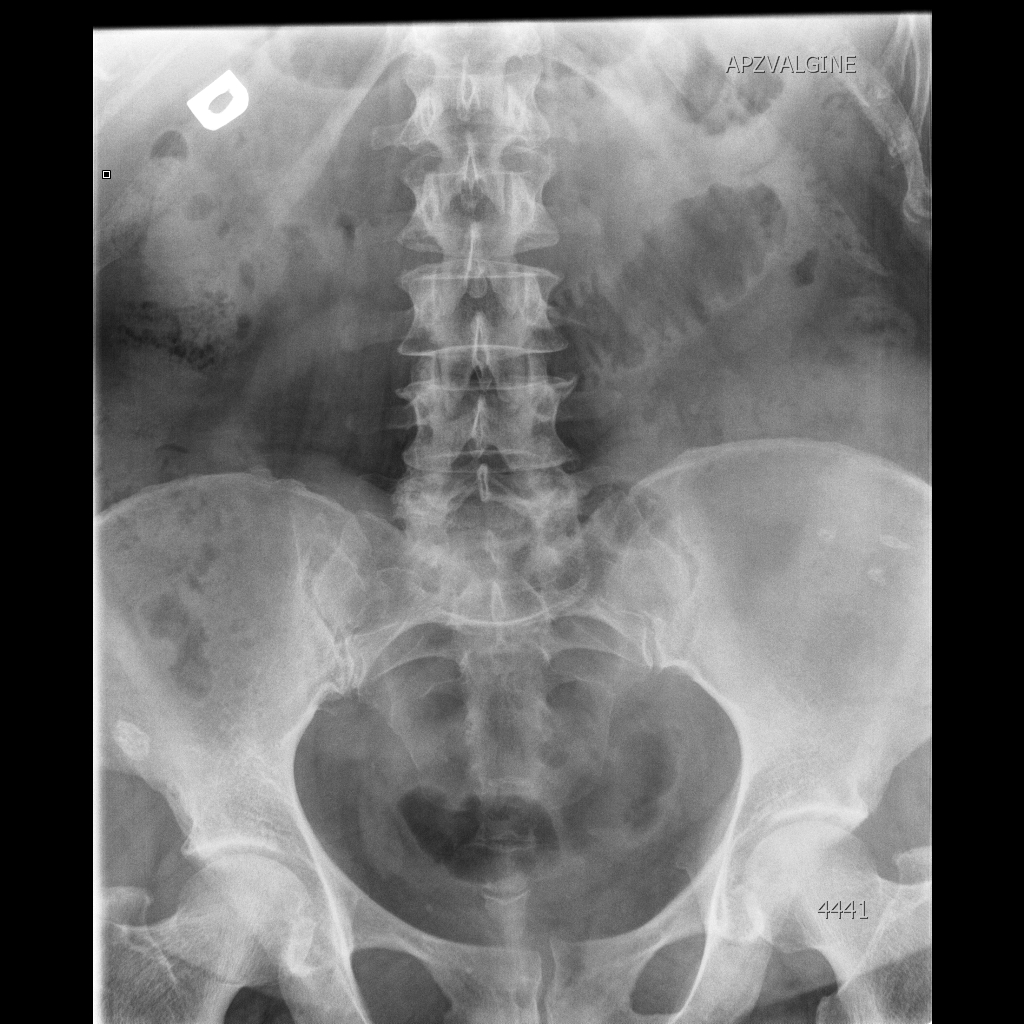

Киста, симулирующая гидрокаликоз

jul232014100551_8.jpg

Через 5 дней выложу урограммы.

Обзорная

Киста имхо очевидна. Без связи с чашкой.